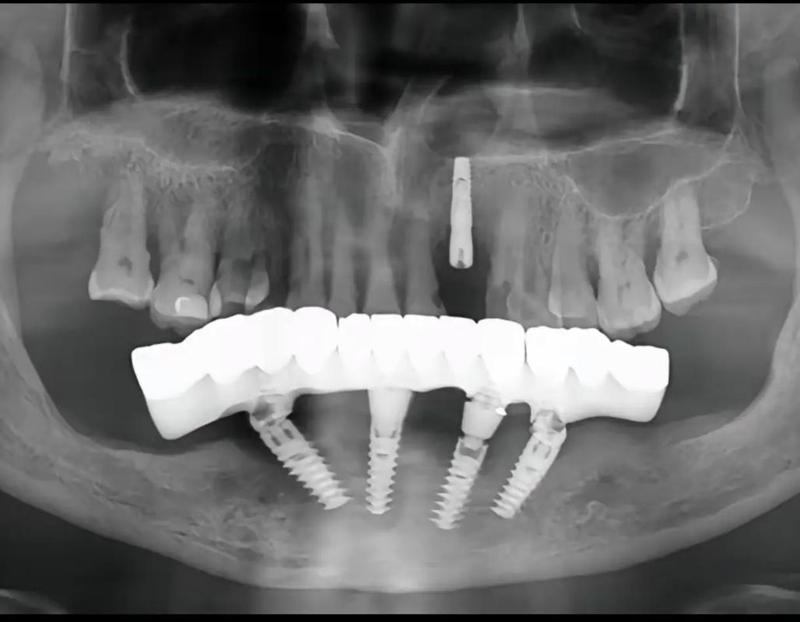

专注口腔美容的专科机构,拥有周国欣主任领衔的种植团队,开展ALL-ON-4全口种植项目。特色项目包含前牙美学区即刻种植(单颗12800元起)和隐形矫正(29800元起)。医院引进瑞士士卓曼种植系统,配备独立消毒供应中心,严格执行六手操作规范。